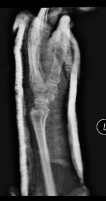

术后第一天,患者意识恢复清醒,复查头部CT提示颅内血肿清除彻底。全腹CT、双腕关节CT显示:肠管管壁明显水肿增厚,邻近肠系膜肿胀,肠间隙模糊,盆腔少量积液,腹腔内未见游离积气,提示肠管或肠系膜损伤;右侧月骨脱位,左侧桡骨远端骨折。

胃肠小儿外科、脊柱创伤外科会诊讨论,确定了分期治疗方案。术后第2天,胃肠小儿外科张达主任医师在全麻下为患者行小肠破裂修补术+腹腔脓肿清除术+肠粘连松解术+肠排列术。脊柱创伤外科薛建康主任医师为患者行左侧桡骨骨质手法复位后石膏外固定,后行右月骨脱位切开复位。

(左侧桡骨远端骨折) (手法复位及石膏外固定后位置良好)